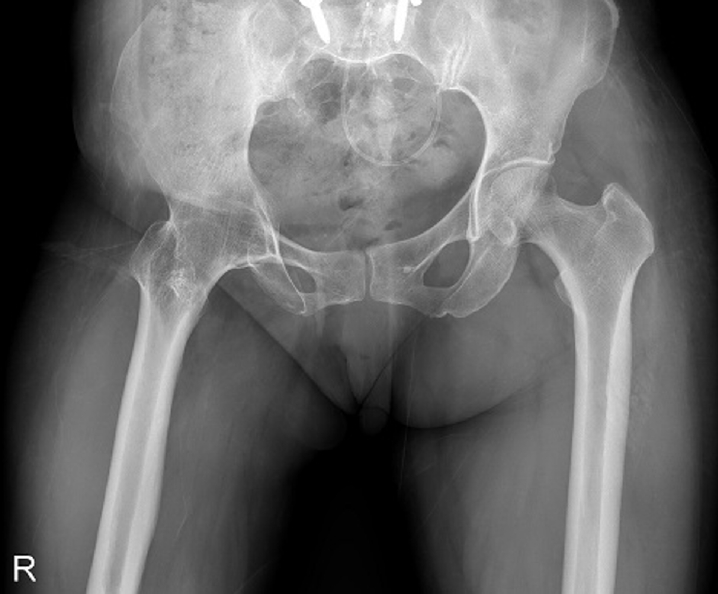

Previous studies have extensively examined the association between femoral insufficiency fractures and prolonged bisphosphonate therapy. However, alternative etiologies remain insufficiently characterized. This study aimed to analyze non-pharmacologic factors associated with femoral insufficiency fractures, with particular emphasis on paradoxical cortical hypertrophy and altered biomechanical load distribution. We reviewed three cases of femoral insufficiency fracture that were surgically treated at our institution between January 2018 and January 2022. None of the patients had a history of bisphosphonate use. Clinical histories—including underlying comorbidities, prior surgical procedures, and radiographic findings—were evaluated. Serial radiographs obtained before and after fracture occurrence were analyzed to characterize fracture morphology and associated cortical changes. Case 1 involved a patient with post-traumatic hip synostosis; case 2 involved a patient with osteogenesis imperfecta; and case 3 involved a patient who had previously undergone intramedullary nailing for an intertrochanteric fracture. Lateral femoral bowing and cortical hypertrophy preceded fracture development in two cases, whereas focal cortical hypertrophy at the distal locking screw site was observed in the third case. No history of bisphosphonate therapy was identified in any patient. Fractures developed at sites characterized by increased cortical remodeling and abnormal load concentration. Femoral insufficiency fractures can occur in the absence of bisphosphonate therapy. Paradoxical cortical hypertrophy and altered biomechanical force distribution appear to be important contributing factors. Level of evidence: IV.